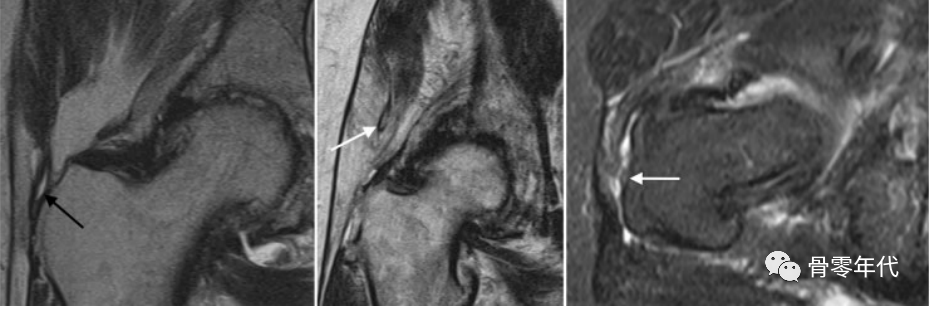

部分厚度肌腱撕裂的特征是T2高信号或纤维性缺损,残留的纤维附着在骨部。肌腱全层撕裂的特征是肌腱脱落,肌腱撕裂区域出现光秃的粗隆。肌腱延长是臀中肌外侧束撕裂的可靠征象,在冠状位MR图像上显示最佳。肌腱撕裂主要发生在潜在的严重肌腱病变,并经常与滑囊炎共存。最常见的情况是外展肌撕裂发生在臀中肌腱的外侧部分,并可能延续到臀小肌腱。在无症状的髋关节中,臀中肌和小肌腱的部分撕裂分别占25%和11%。

(a)冠状面T2加权像上的外侧臀中肌部分厚度撕裂(箭头),以及(b,c)外展肌腱的全层撕裂(b和c中的箭头指向臀中肌外侧),臀中肌明显回缩,如冠状面T2加权像(b)和轴向质子密度加权脂肪饱和图像(c)所示。

71岁女性臀小肌腱部分厚度撕裂(a和b中的箭头):(a)脂肪饱和冠状质子密度加权图像和(b)轴位T2加权脂肪饱和图像,伴有明显增厚和相关的小粗隆滑囊炎(b,虚线箭头)。(c)臀小肌腱在矢状位T1加权像上信号强度增加(星号)反映潜在的肌腱病变。